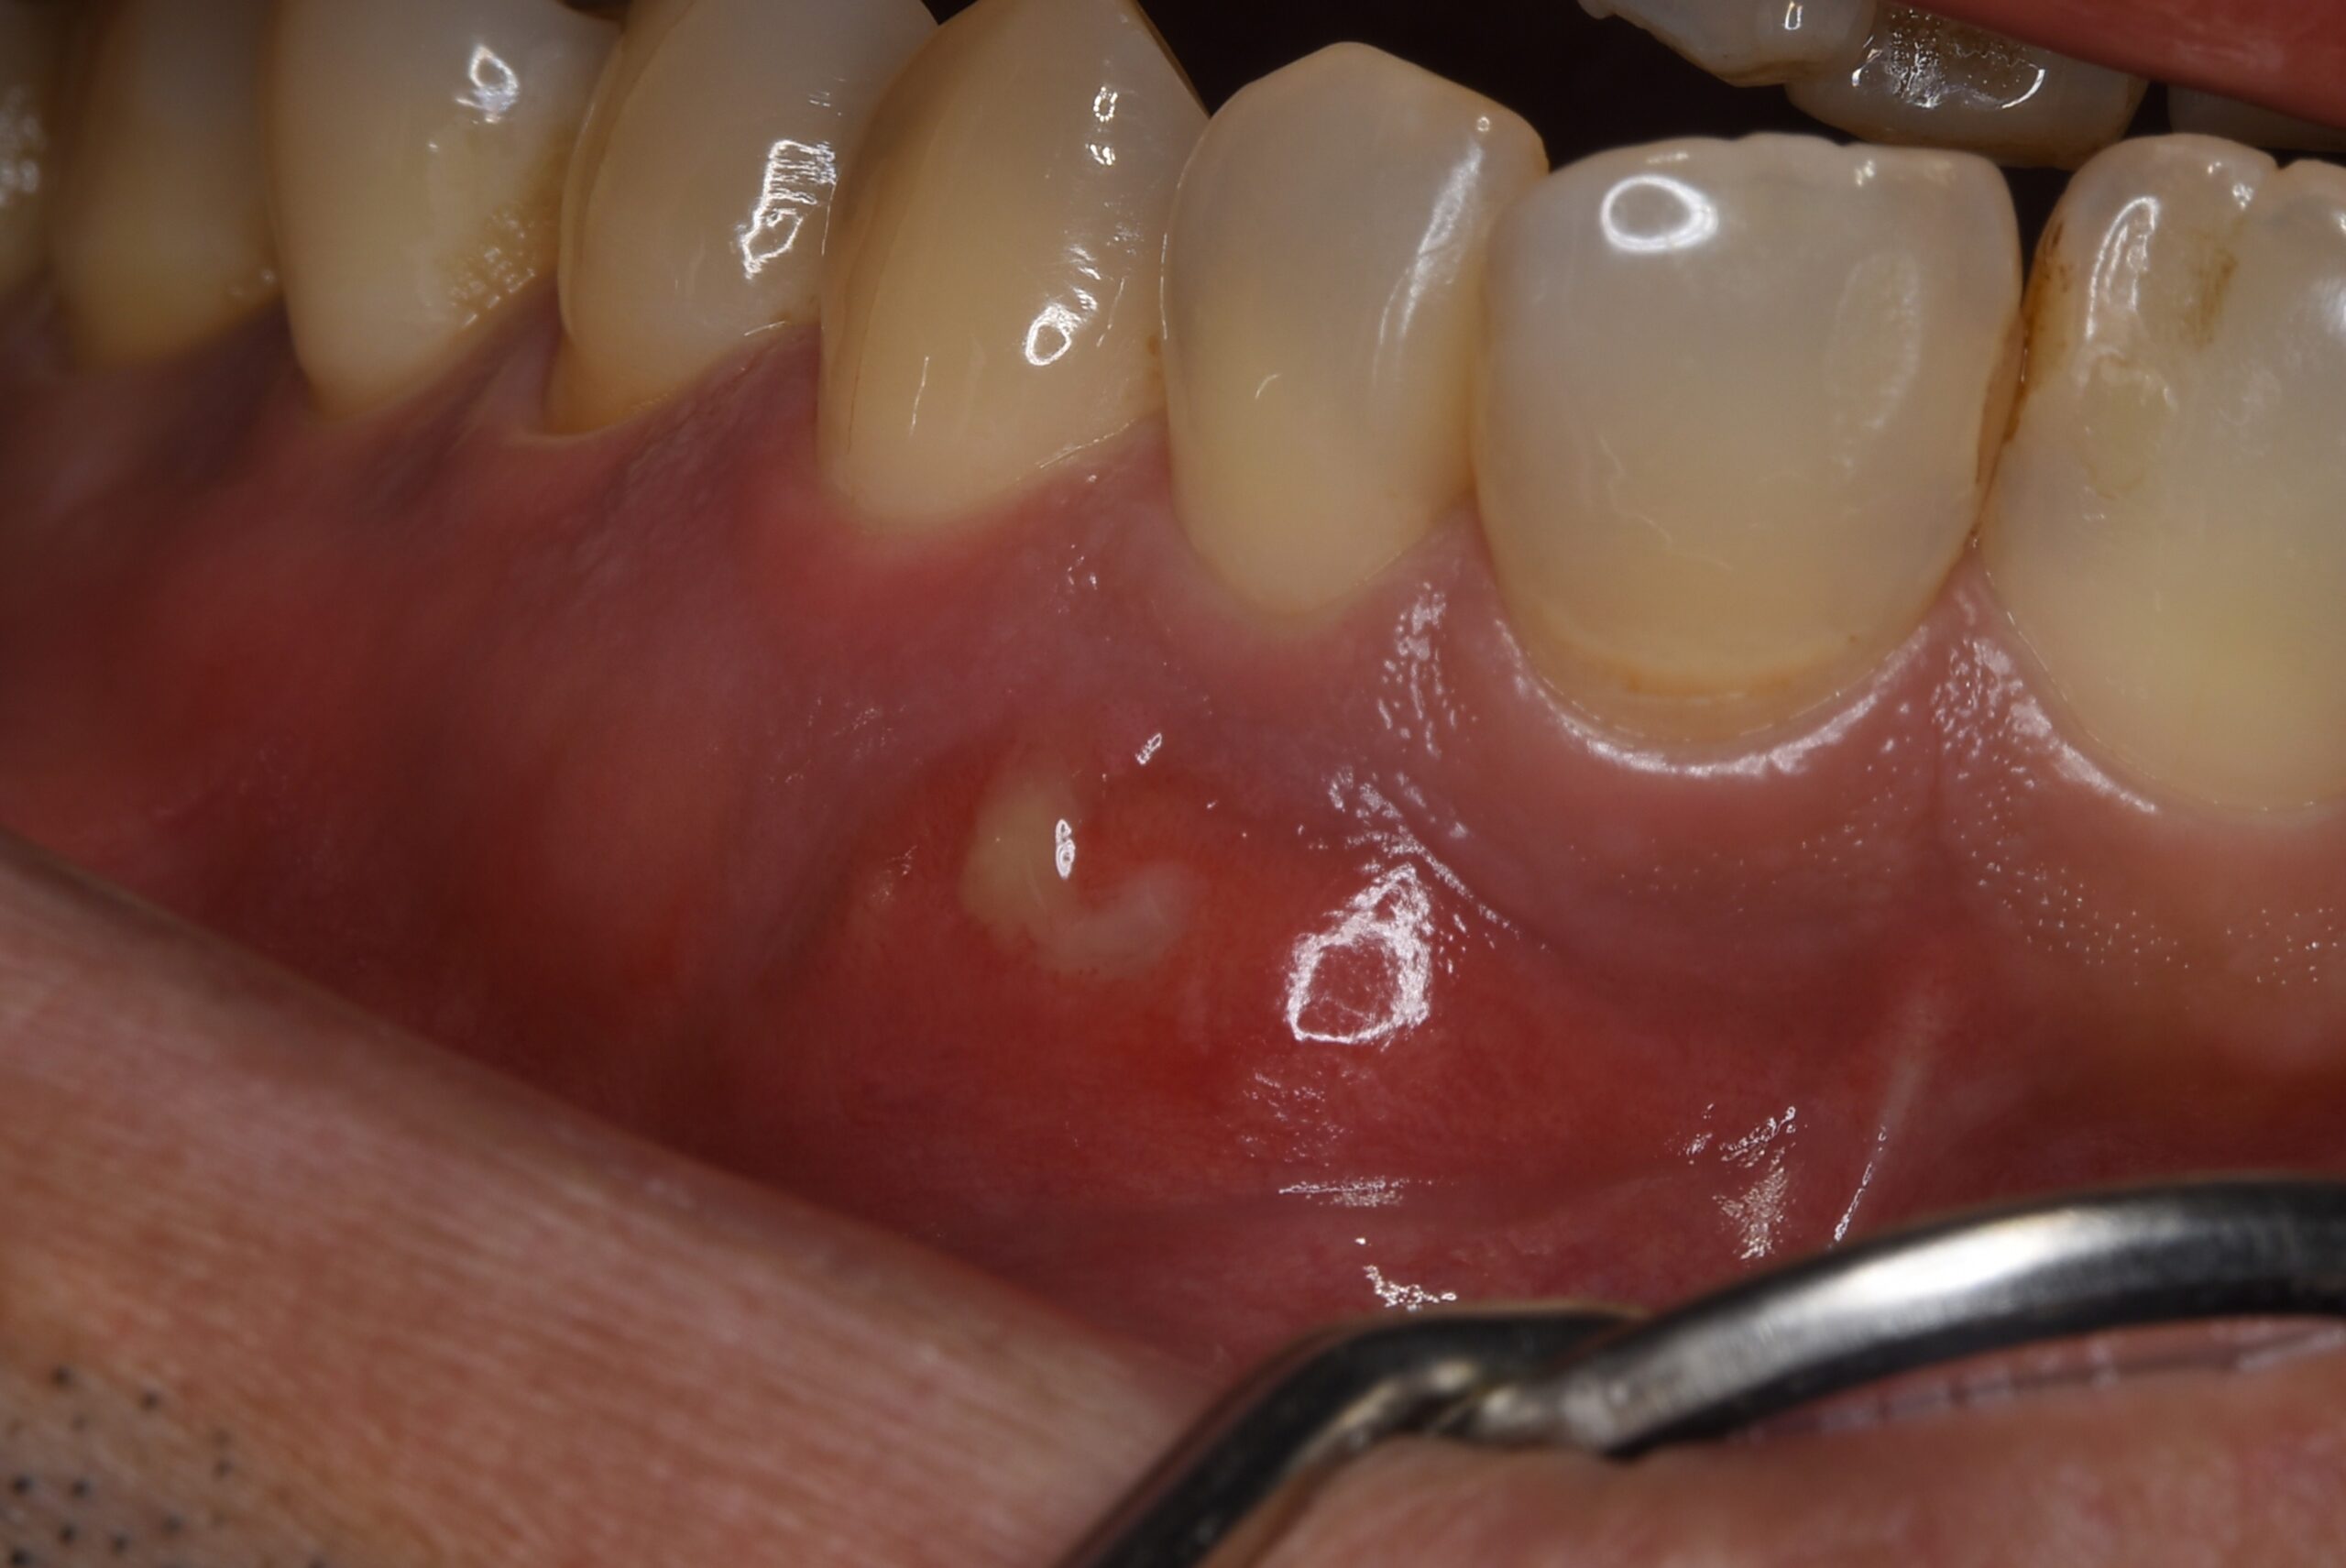

術前

歯肉は腫脹し排膿していた。